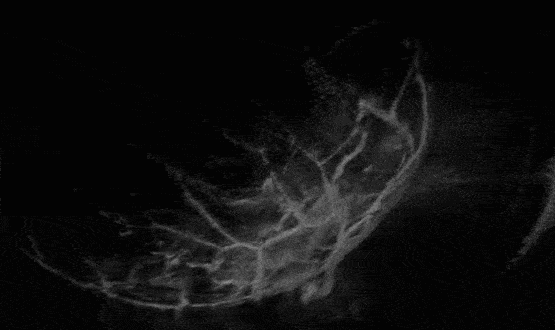

通過 3D-PACT 獲得的大鼠心臟結(jié)構(gòu)圖像

林勵教授及其團隊改進開發(fā)的3D-PACT,擁有一個超大的超聲孔徑,可以提供半全景超聲探測視角,有助于減弱肋骨和肺部組織對超聲信號的遮擋。同時,采用波長為 1064 納米的光照,在生物組織中經(jīng)過相對較少的散射,達到更深的穿透深度,覆蓋整個心臟。此外,在掃描過程中,通過同步 3D-PACT 與心電圖測量,利用心跳周期引導(dǎo)光聲信號時間門控采集。進而無創(chuàng)、清晰地展示了活體大鼠心臟的整體解剖結(jié)構(gòu)和功能特性。據(jù)了解,該團隊研發(fā)的 3D-PACT 擁有非常廣泛的應(yīng)用場景,可以用于大多體表病灶,包括乳腺癌、甲狀腺癌、皮膚癌等,同時也具備成像嬰幼兒心臟和心血管的潛力。